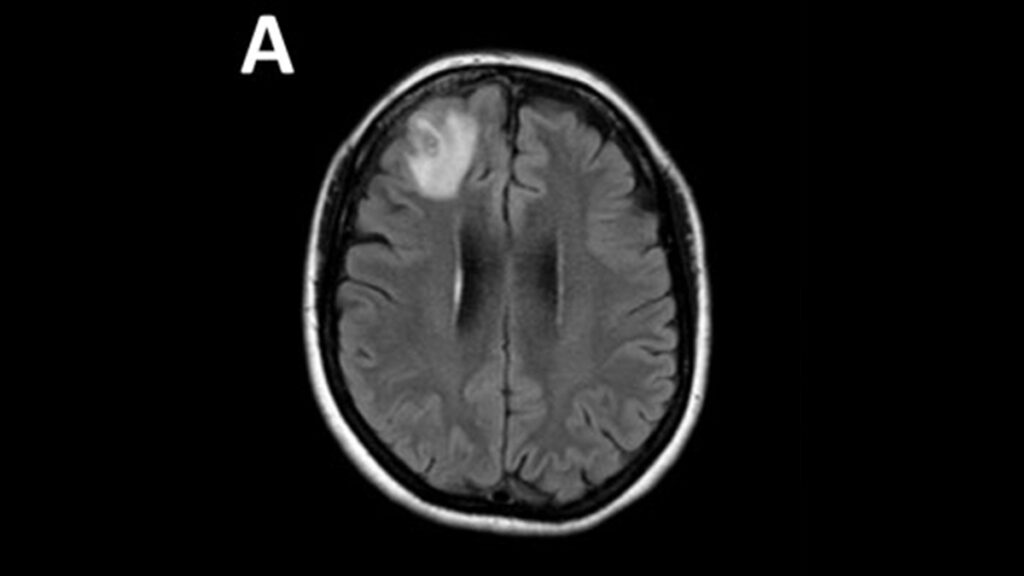

Por su parte, el médico infectólogo Sanjaya Senanayake, coautor del estudio, explicó que ante los irregulares síntomas, esperaban que la paciente tuviera un tumor, cáncer o una afección inmunológica. Pero cuando la operaron del cerebro en busca de un tumor, se hallaron con algo completamente inesperado.

Finalmente, la doctora Bandi realizó la cirugía cerebral de la paciente, pero cuando esperaba encontrar un tumor, dio con el gusano alojado en el cerebro.

"Usé pinzas para sujetar tumores y saqué algo que definitivamente no esperaba: un cordel lineal y serpenteante. Y el médico asistente dijo: '¿Es una arteria?', porque eso es lo que parecía. Pero yo le dije: 'No es una arteria. No estamos cerca de ninguna arteria'. Y me di cuenta de que se movía e inmediatamente dije, 'por favor, ¡sácalo de mis pinzas!'. Así que lo pusimos rápidamente en un recipiente de patología y era un gusano que se movía vigorosamente", contó a DW.